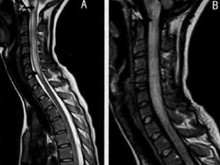

系统性红斑狼疮性脊髓病

(又名全身性红斑狼疮所致脊髓病)

系统性红斑狼疮(SLE)脊髓病,是的SLE脊髓病变表现。SLE它是一种由多种因素...